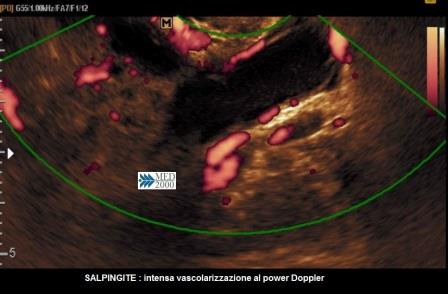

Il segno ecografico caratteristico delle fasi iniziali è la presenza di una tumefazione annessiale adiacente all'ovaio, isoecogena col miometrio, di forma tubulare o ovoidale, non sempre facilmente distinguibile dall'intestino; un operatore esperto può coglierne i segni distintivi: assenza di peristalsi, dolore evocato dalla pressione mirata con la sonda endocavitaria (pain mapping), presenza di una discreta o ricca vascolarizzazione al color/power Doppler. Successivamente, con la formazione di una piosalpinge, la tuba si distende assumendo una morfologia tubuliforme per la presenza di liquido ad aspetto ipoecogeno, disomogeneo, dovuto all'accumulo di pus e sangue e la parete tubarica si ispessisce per l'edema conseguente alla flogosi; alcuni Autori hanno proposto un cut-off di 5 mm. per indicare l'ispessimento della parete tubarica, mentre altri si rifanno all'impressione soggettiva dell'ecografista. In sezione trasversa si osservano delle protrusioni endoluminali iperecogene legate all'edema delle pliche endosalpingee che danno origine ad un segno ecografico caratteristico, il "segno della ruota dentata".

Nella fase acuta dell'annessite lo studio con il color/power Doppler consente di evidenziare una intensa vascolarizzazione tubo/ovarica con flussi a bassa resistenza; non vi sono allo stato valori standard di RI e PI per cui è importante l'esperienza dell'operatore nella valutazione della ipervascolarizzazione caratteristica della fase acuta delle annessiti.